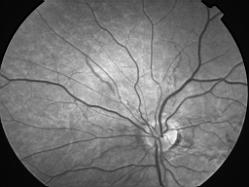

ASSOCIATION STRIES ANGIOIDES ET DYSROPHIE MACULAIRE RETICULEE

NEOVASCULARISATION